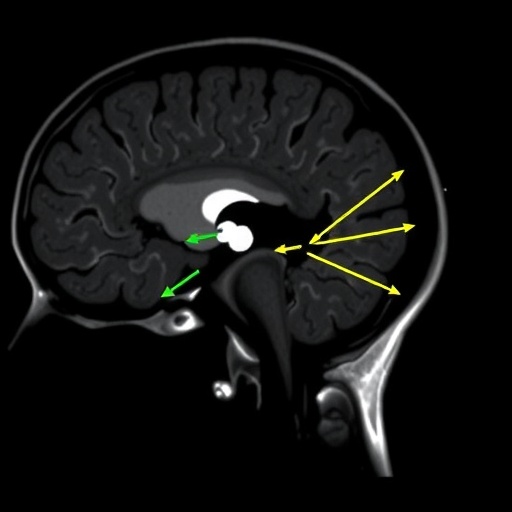

Axial MRI Reveals TMJ Condyle and Muscle Angles